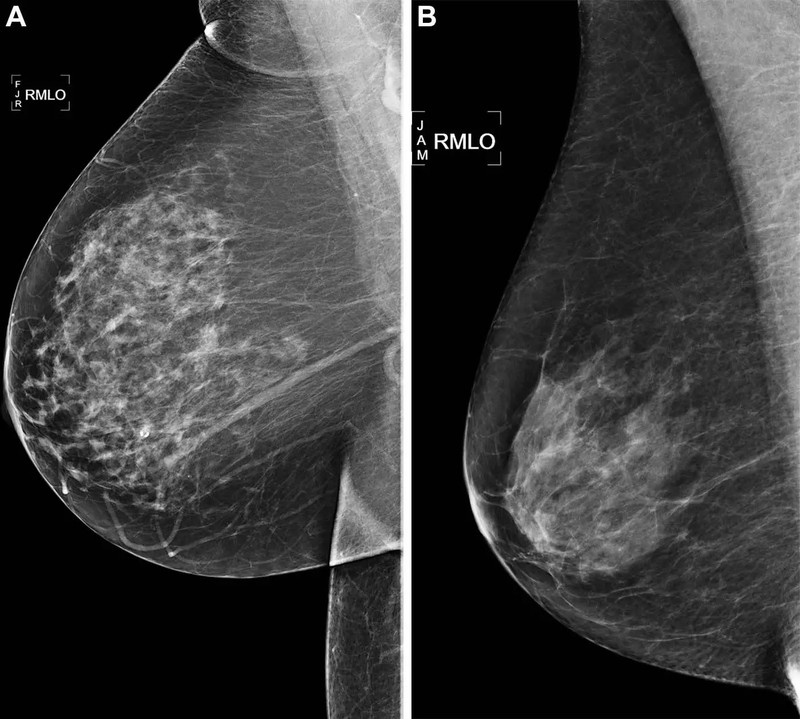

Trong nghiên cứu hồi cứu (bộ dữ liệu những bức ảnh quang tuyến vú chụp trước đó 5 năm), TS Arasu đã sử dụng bộ dữ liệu kết quả chụp quang tuyến vú 2D, đã sàng lọc âm tính (không có bằng chứng rõ ràng về ung thư) được thực hiện tại Kaiser Permanente ở Bắc California vào năm 2016.

Trong số 324.009 phụ nữ được sàng lọc bằng ảnh quang tuyến vú năm 2016, đáp ứng đầy đủ những tiêu chí nghiên cứu, các nhà khoa học lựa chọn dữ liệu của một nhóm phụ nữ ngẫu nhiên, 13.628 người để đào tạo AI và phân tích.

Nhóm nghiên cứu cũng sử dụng dữ liệu của 4.584 bệnh nhân từ nhóm phụ nữ đã chọn cho nghiên cứu này. Nhóm bệnh nhân này đã được bác sĩ chẩn đoán mắc bệnh ung thư trong vòng 5 năm kể từ lần chụp quang tuyến vú đầu tiên năm 2016. Tất cả những phụ nữ này đều được theo dõi cho đến năm 2021.

Nhóm nhà khoa học đào tạo các mô hình AI xác định rủi ro bằng 5 thuật toán trong đó 2 thuật toán hàn lâm do các nhà khoa học phát triển và sử dụng, 3 thuật toán có sẵn trên thị trường. Sau đó, sử dụng những bức ảnh chụp quang tuyến vú sàng lọc năm 2016, bằng các mô hình AI, nhóm nhà khoa học ước tính rủi ro ung thư vú trong khoảng thời gian 5 năm. Điểm rủi ro sau đó được so sánh giữa các thuật toán AI và với điểm rủi ro lâm sàng BCSC.